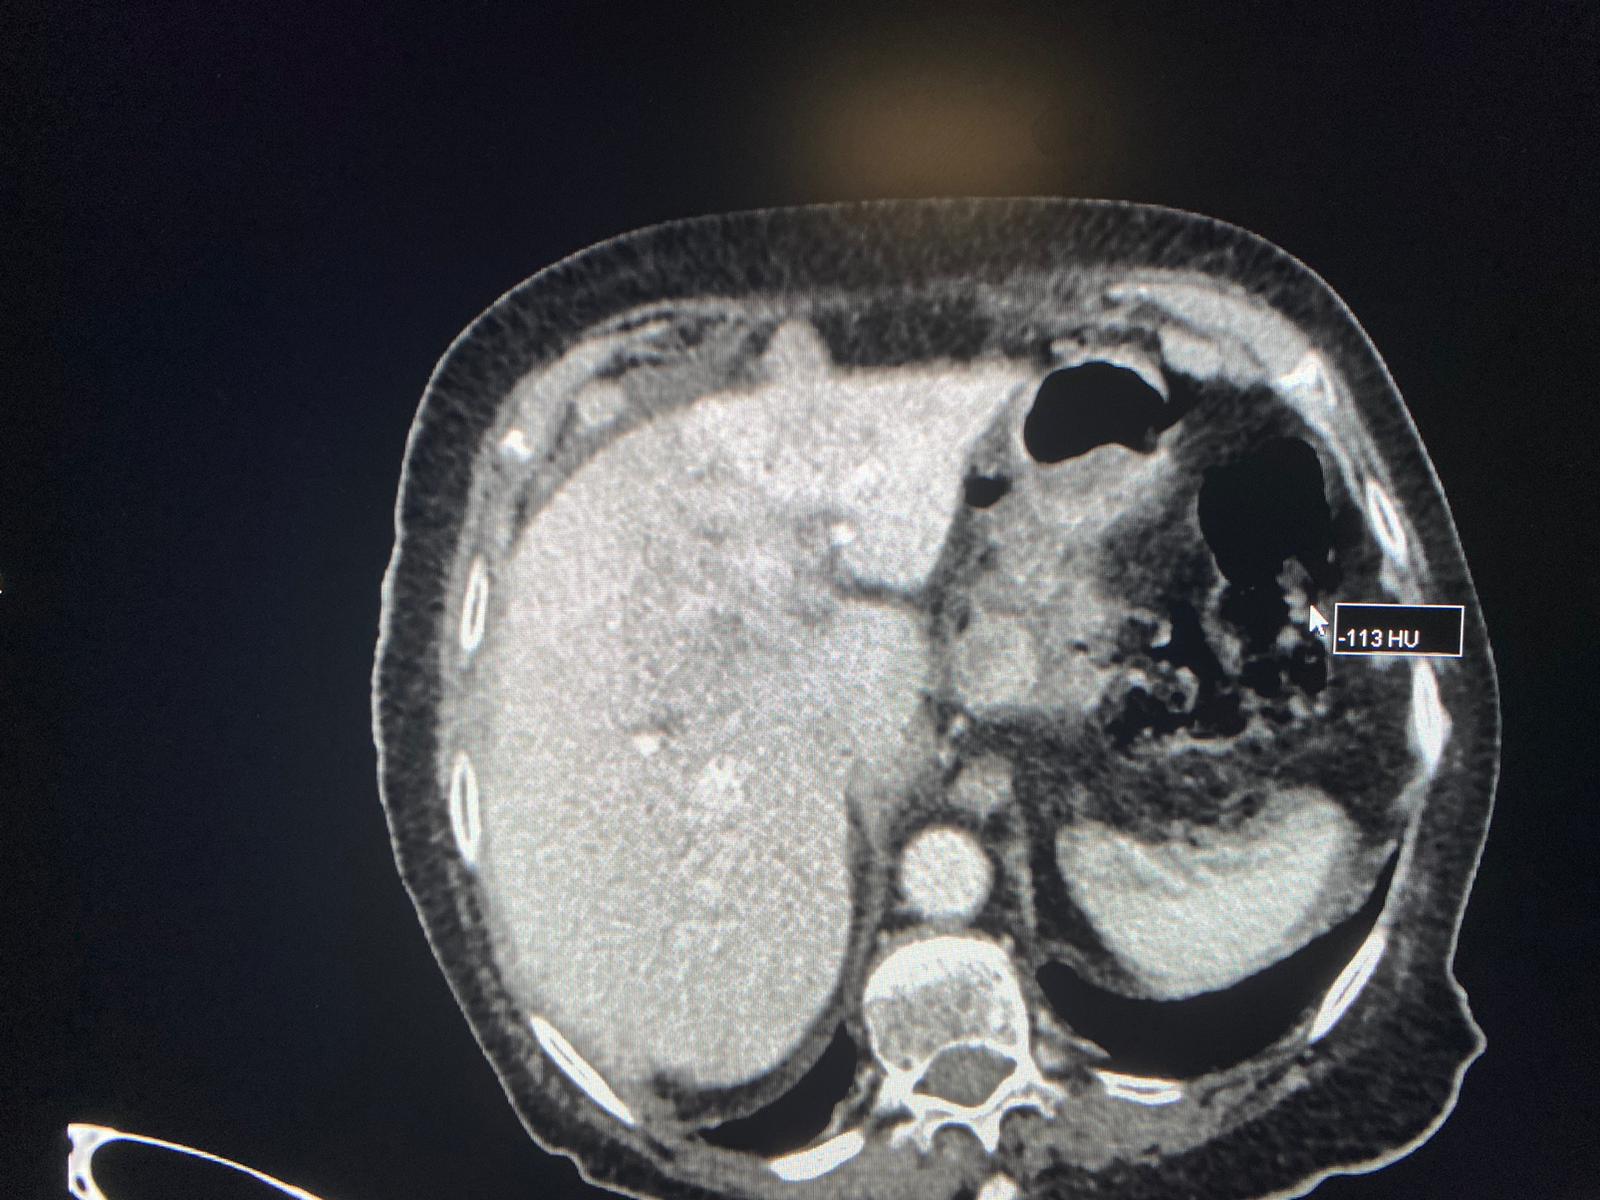

| Llaman por sospecha de colecisitis en mujer de 95 años. Se hace el TC y vemos una gran masa heterogènea hepática, que condiciona dilatación de via biliar intra y extra, junto con múltiples implantes perihepàticos, periportales, periesofágicos, intrapelvicos… Se sospecha de colangiocarcinoma, menos probable hepatocarcinoma. |